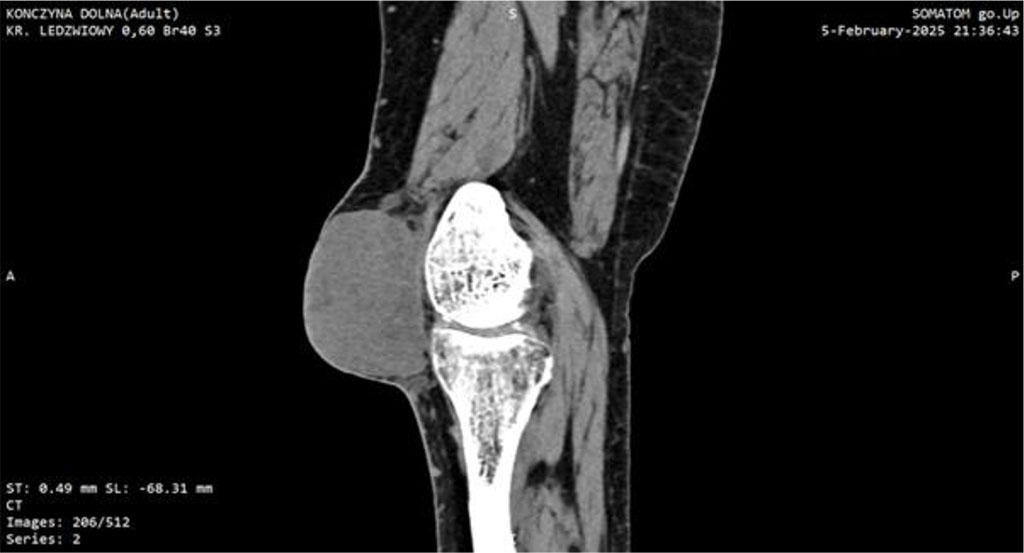

Within one month post-surgery, the lesion expanded dramatically to ~7 cm, became markedly erythematous, cyanosed, and showed areas of necrosis. This raised a suspicion of a malignant tumor which led to extended diagnostic. CT imaging identified a soft-tissue mass with dense fluid components (73 × 40 × 70 mm), without patellar destruction or intra-articular effusion (Fig 1, 2).

Figure 1: CT scan of the knee joint with Myxofibrosarcoma (MFS). Sagittal plane.